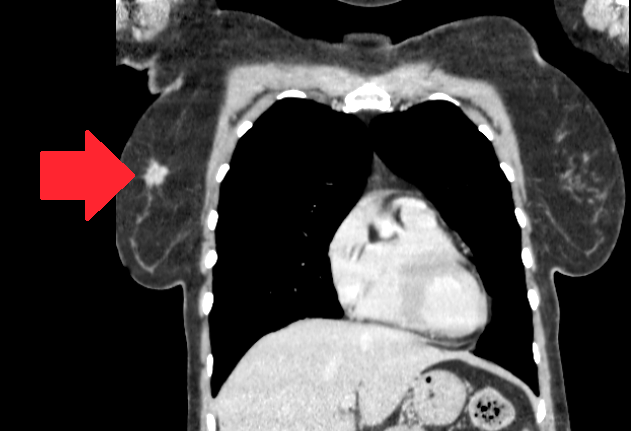

Компьютерная томография с контрастированием позволяет прекрасно визуализировать опухоль в молочной железе

По данным компьютерной томографии всего тела с контрастированием признаки отдаленного метастазирования выявлены не были, но определился округлый подозрительный лимфоузел в правой подмышечной области. Размеры опухоли по КТ определились как 19х13.5х19 мм.